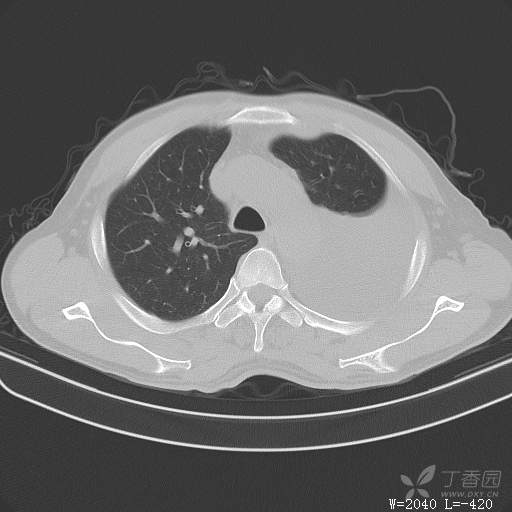

简要病史:胸闷、憋气伴低热1月

体格检查:T:37.6℃;P:92次/分;R:20次/分;Bp:100/60mmHg,神清,呼吸平稳,周身未触及肿大淋巴结,右肺及左上肺叩诊清音,左下肺叩诊浊音,右肺及左上肺呼吸音粗,左下肺未闻及呼吸音,心率92次/分,律齐,无杂音。腹部平坦,软,全腹无压痛,无反跳痛及肌紧张,肝脾肋下未触及,双下肢无水肿。

临床诊断:左侧胸腔积液

治疗经过:胸水引流。胸水白蛋白23.8克/升,乳酸脱氢酶275单位/升,胸苷激酶182单位/升,胸水外观黄色混浊,总细胞4320个/微升,白细胞4320个/微升,单核细胞80%,多核细胞20%。考虑结核性胸膜炎,结果查肿瘤标志物、胸水细胞学阴性,胸水TB—DNA阴性,结核菌素试验+,结核抗体阴性,TB-SPOT阴性,胸膜活检阴性。怎么办?